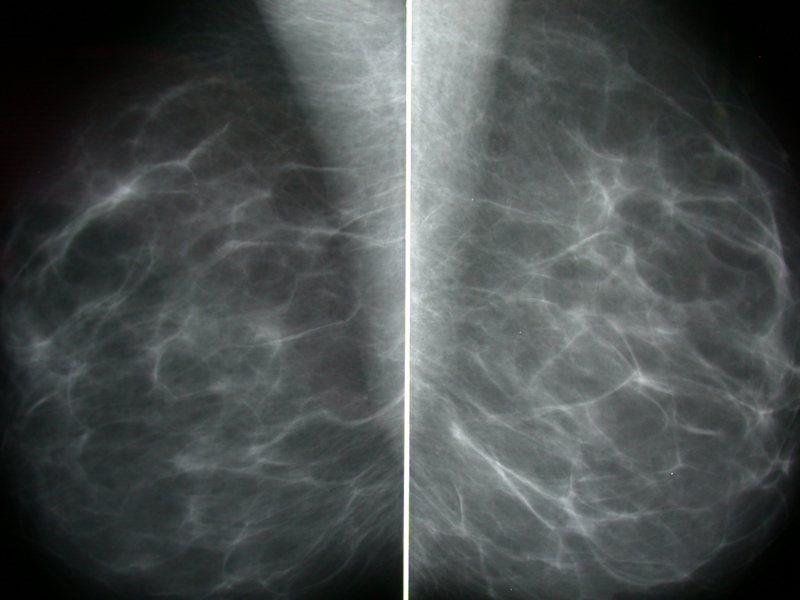

בתמונה: ממוגרפיה ללא טיפול הורמונלי